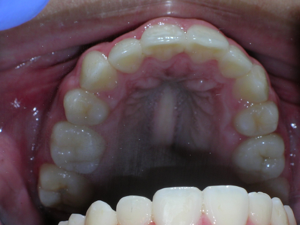

First Premolars were removed. We used an anchor device on the top jaw known as a “Nance” holding arch to help us retract the canines into the first premolar space. The holding device is used to reduce shifting of the top back teeth forward.

Here is what he looked like on the day that the braces were removed.

In the final photo, you can see the bonded retainer we used. A top nighttime removable retainer was made.